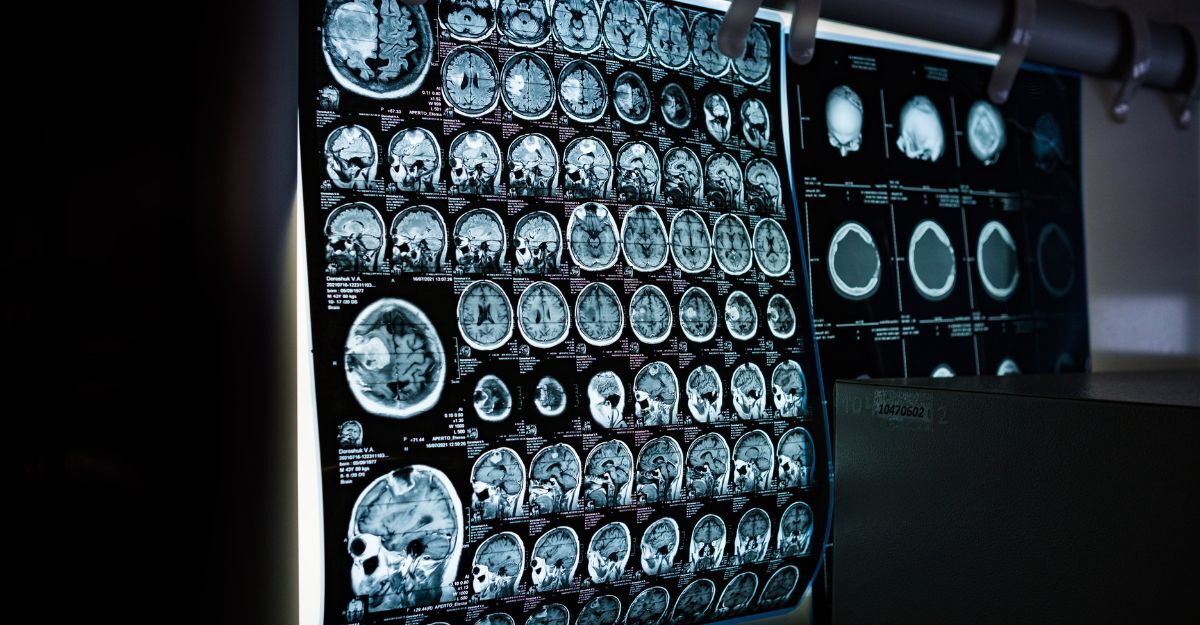

Nel tempo, questi fattori possono compromettere il flusso sanguigno cerebrale, favorendo microlesioni, ischemie silenti e cambiamenti strutturali che incidono sulle funzioni cognitive.

L’obesità, dunque, non riguarda soltanto il metabolismo o il sistema cardiovascolare. Le sue conseguenze possono estendersi anche al cervello, influenzando la salute cognitiva nel corso della vita.